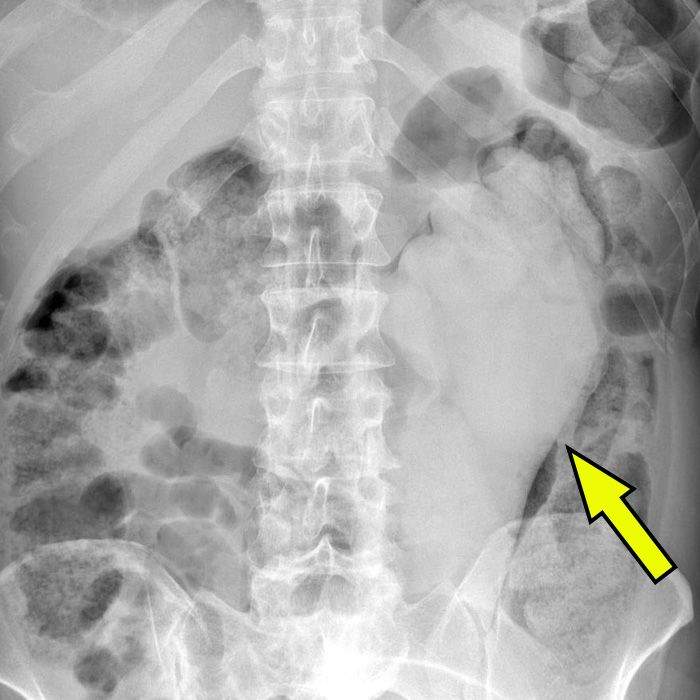

以前阿漆也記得分享過幾次,就是國外有不少人身體裡有異物拿不出來,因此必須到醫院請求幫助,當醫生X光照下去的時候,才發現患者身體裡的東西是什麼?像這樣的圖片非常多,今天阿漆就找了一些給大家看

▼雞蛋這個有點厲害,難道放的過程不會不小心弄破嗎?

圖片來自:ems1